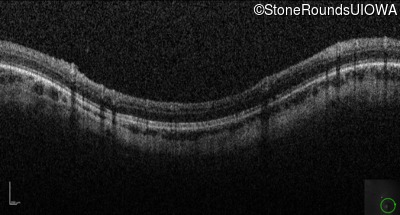

Optical Coherence Tomography - Right - 10/160 sc

Exemplar